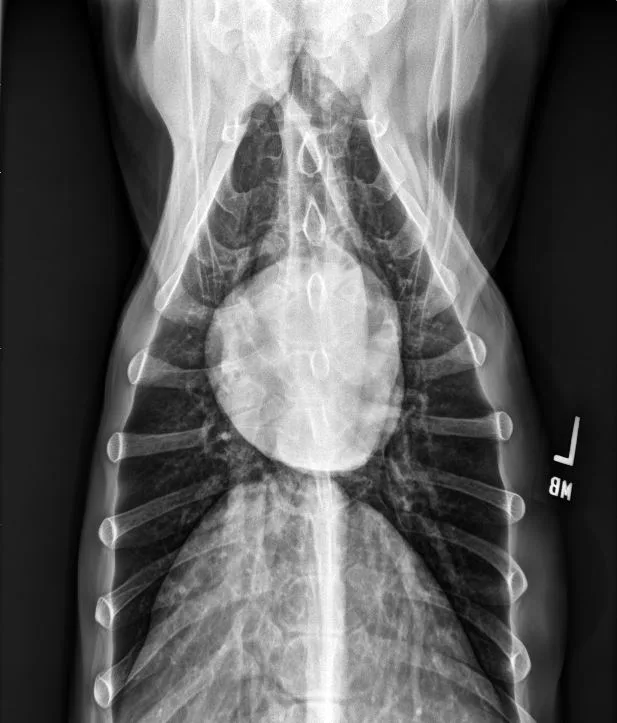

A subset of patients with acquired heart disease may develop left-sided congestive heart failure (CHF). In addition to left-sided cardiomegaly, dogs with active CHF secondary to MMVD commonly exhibit lobar pulmonary venous enlargement on radiographs, as well as an interstitial to alveolar radiographic lung pattern that typically develops in the perihilar region and right caudal lung lobes (Figure 8); however, in dogs with DCM, this lung pattern may be seen in the ventral lung lobes (Figure 9). The radiology lung score is an objective method to quantify severity but was not associated with the recurrence of CHF or survival in one study.16 Dogs administered diuretics may not have pulmonary venous dilation, and some dogs with CHF secondary to acute increase in left atrial pressure (eg, aortic valve endocarditis, chordae tendineae rupture) may not have significant cardiomegaly.

FIGURE 9 DV (left) and right lateral (right) projections consistent with left-sided CHF in a dog with advanced DCM. Perihilar to ventral distribution of the severe interstitial to alveolar pulmonary pattern is present in addition to cardiomegaly. VHS, VLAS, M-VLAS, and VRHi collected from the right lateral view are 11.5, 2.1, 4.1, and 3.1, respectively. (Note: The DV image is flipped to display the right side of the patient to the left.)